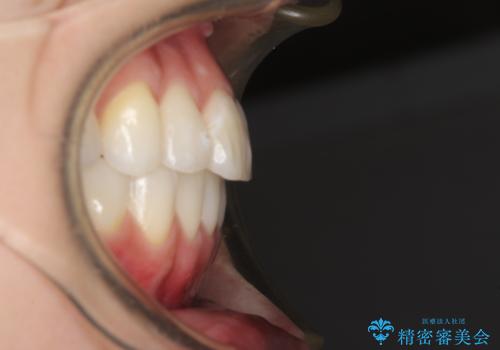

- 前歯のデコボコと残っている乳歯の部分へのインプラント治療を希望して来院された患者様です。

当初は目立たない上下裏側矯正を希望されていましたが、歯並びの悪さによる磨き残しが多く、歯肉炎が認められたため、より清潔な環境で治療を進められるインビザラインを選択することとしました。

前歯のデコボコが強かったため、上の奥歯を後方に動かす量が多くなり、結果として2年以上の治療期間を擁することとなりました。